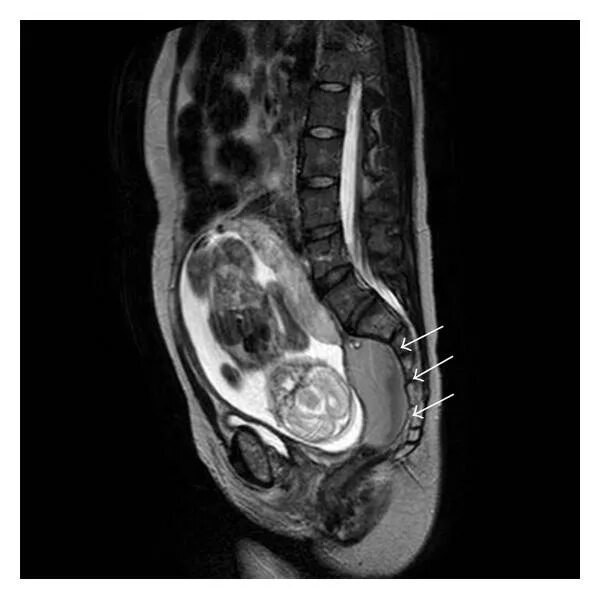

Мрт беременной